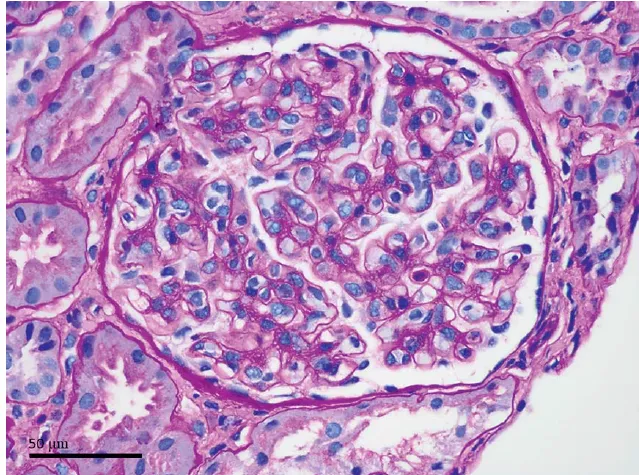

Devido história de lúpus, os achados cutâneos eram preocupantes para calcinose cutânea distrófica. A biópsia

de pele mostrou cristais romboides amarelo-marrom dispostos radialmente no subcutâneo e na derme profunda, circundados por histiócitos consistentes com oxalose cutânea (Figura 3).